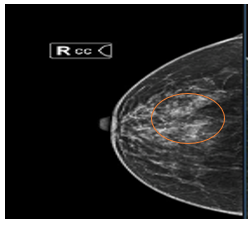

Case lâm sàng: Ứng dụng trí tuệ nhân tạo (Artificial intelligence – AI) trong chẩn đoán và điều trị sớm Ung thư phổi tại Trung tâm Y học hạt nhân và Ung bướu, Bệnh viện Bạch Mai

Theo GLOBOCAN 2022, ung thư phổi đứng đầu về số ca mới mắc (2.480.301 ca mới mắc chiểm 12.4%) và dẫn đầu số ca tử vong (1.817.172 ca tử vong chiếm 18.7%) trên toàn thế giới.  Tại Việt Nam tỷ lệ mắc ung thư phổi xếp thứ ba 13,5% lệ tử vong...